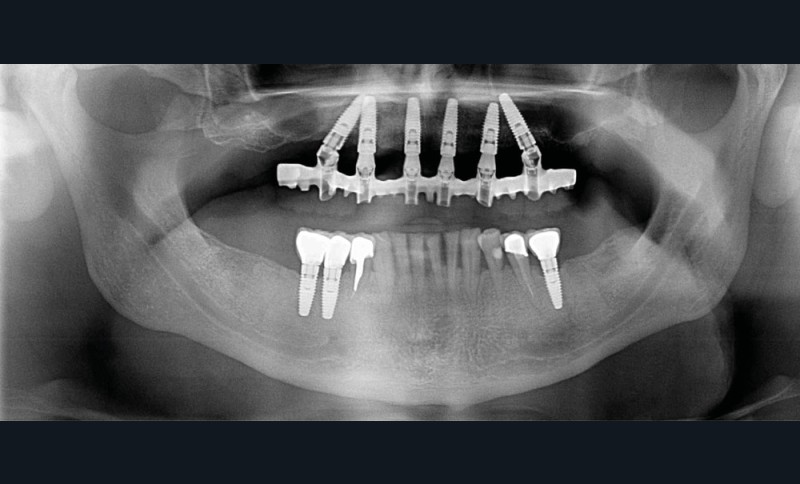

Conséquences en cas d’extraction multiples

Des extractions multiples, simultanées ou graduelles, auront des répercussions sur les dents restantes et sur les tissus mous.

En effet, en cas d’extractions multiples, il est fréquent de constater une diminution de la dimension verticale et une perlèche labiale. Il s’agit d’une chéilite angulaire, liée à des perturbations de la coaptation labiale. Elle est un peu similaire à celle retrouvée chez les patients édentés complets chez qui la dimension verticale est sur- ou sous-évaluée [15].

Des extractions multiples non compensées peuvent aussi occasionner une usure excessive des dents restantes, en raison de leur sollicitation occlusale trop importante.

La prise en charge de ces édentements nécessite un examen complet du site implantaire et de l’environnement [16]. Les conséquences du non-remplacement rapide que nous venons d’énumérer sont à prendre en compte et à corriger pour une intégration optimale de la restauration prothétique implantaire. Ainsi, des corrections orthodontiques peuvent être nécessaires avant ou pendant la thérapeutique implantaire.

Le temps de l’ostéointégration, des versions ou migrations sont aussi possibles et le recours à des dispositifs de maintien de l’espace peut se révéler indispensable (fig. 22 et 23).